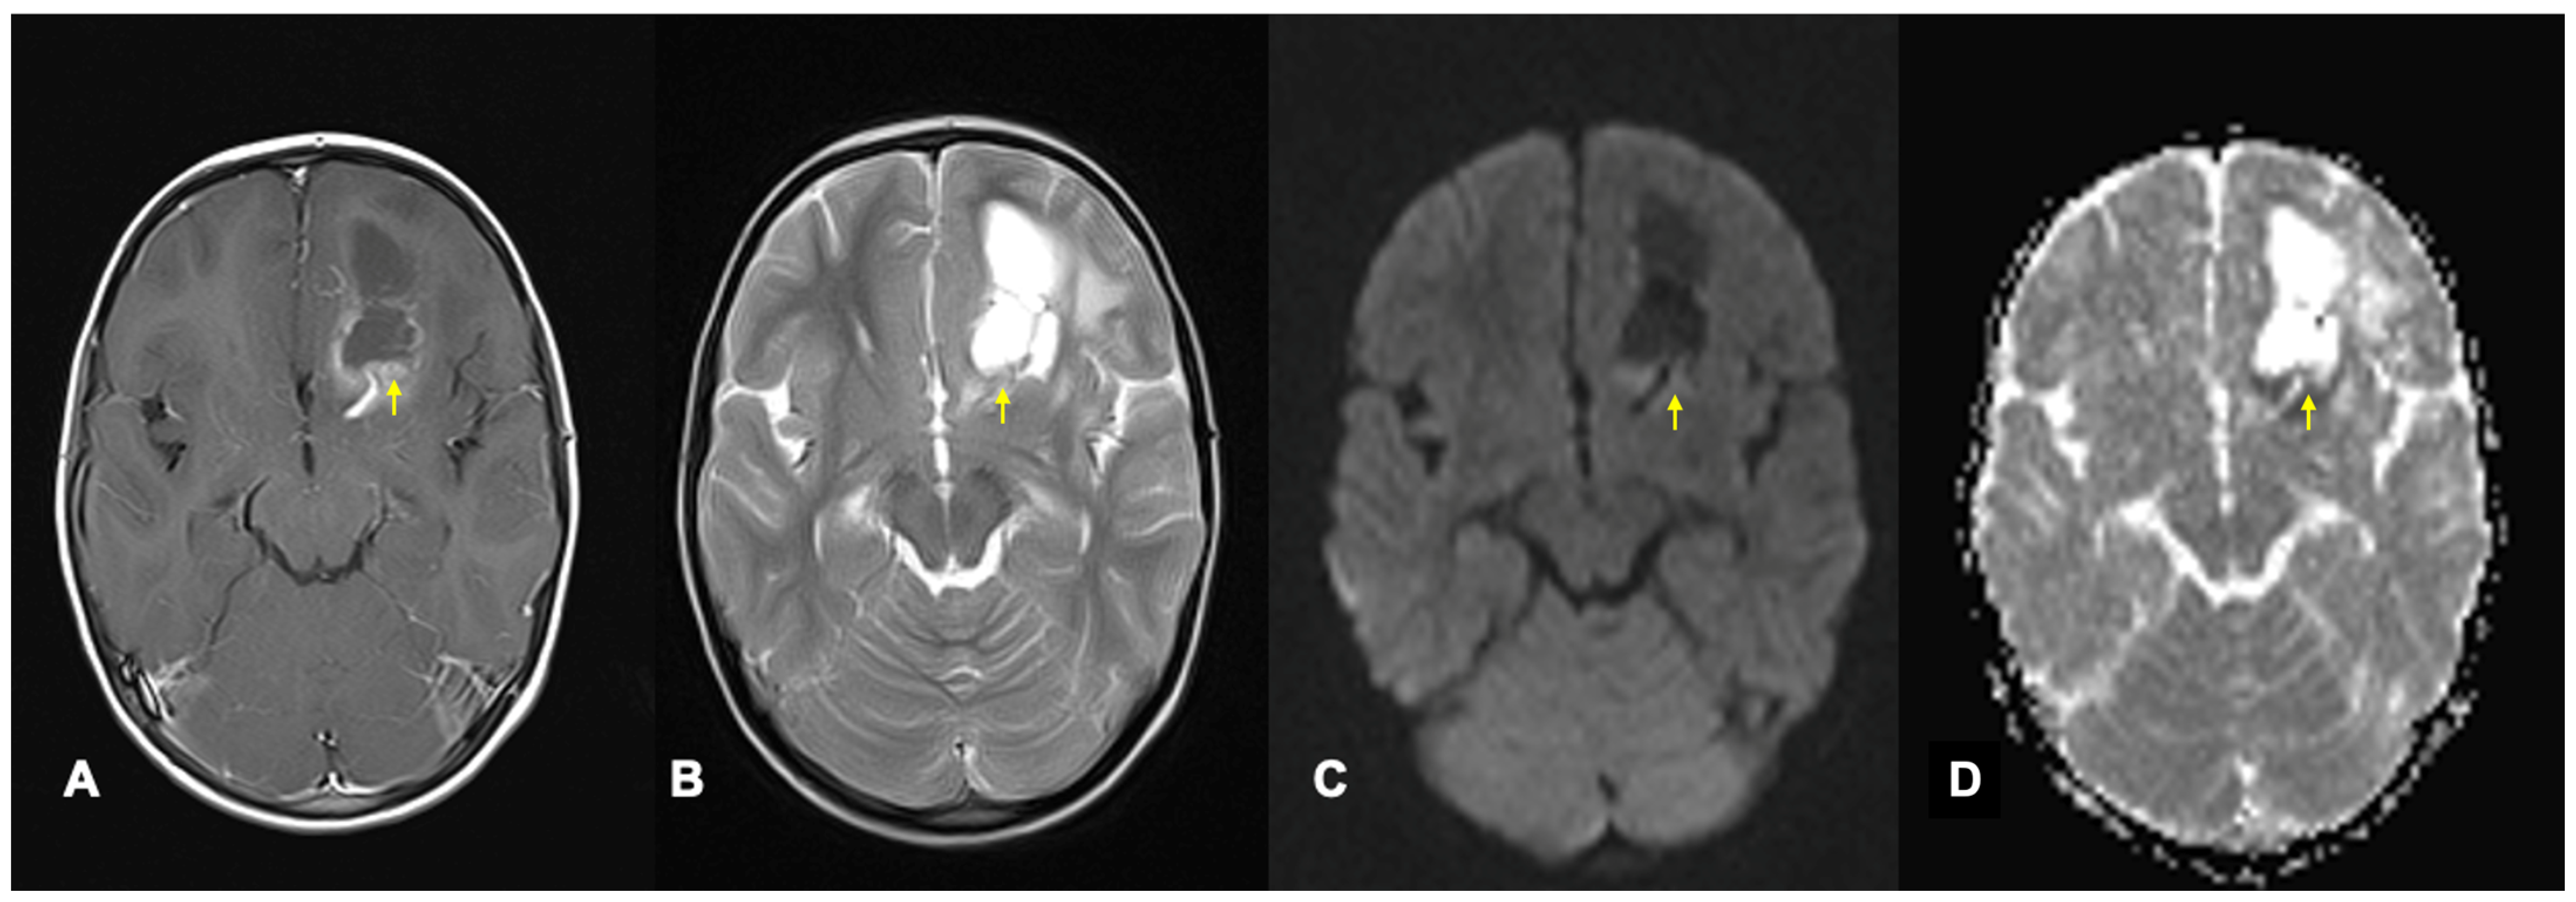

Figure 3.

Axial MRI brain scan of a left frontal CNS neuroblastoma in a 4-year-old girl demonstrating diffusion restriction. (A) shows the post-contrast T1 sequence of a left frontal cystic lesion with an enhancing solid portion posteriorly. (B) is the T2 sequence with relative hyperintensity in the solid portion of the tumour. The solid portion appears hyperintense on DWI (C) and hypointense on ADC (D), in keeping with diffusion restriction. Areas of abnormality discussed are highlighted by yellow arrows. ADC = apparent diffusion coefficient; DWI = diffusion weighted image.